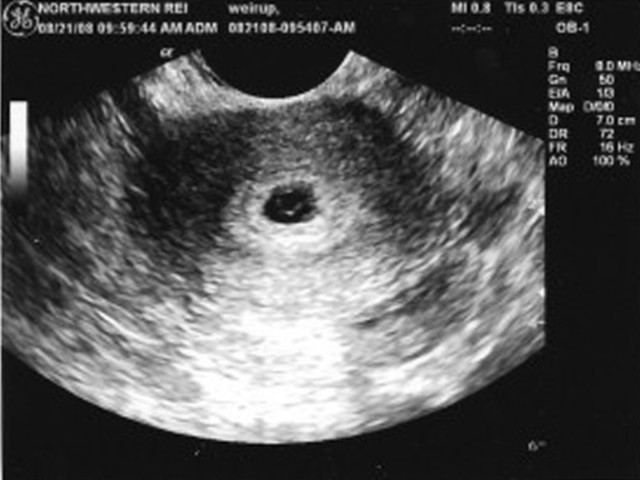

• Перша зустріч

Перша зустріч

В цей день на УЗД жінка вперше бачить свою дитину і дізнається чи все з малюком добре.